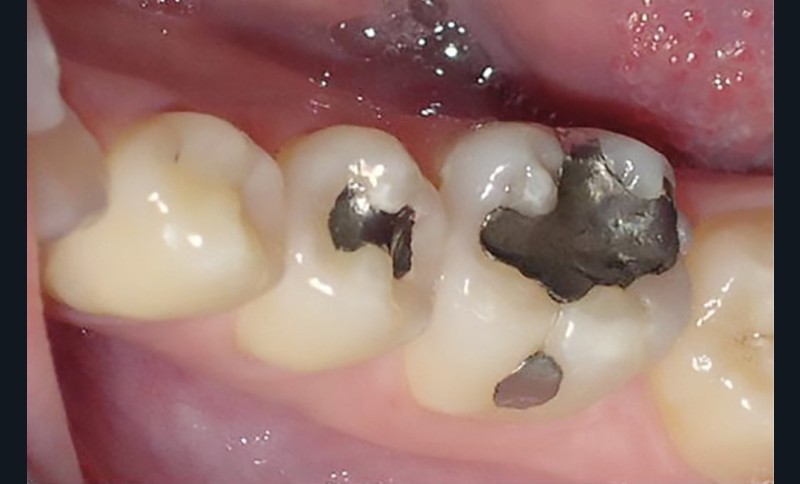

La consommation de produits acides a augmenté de manière exponentielle ces dernières années. On retrouve ceux-ci dans des aliments courants (boissons gazeuses, jus de fruit, en-cas sucré…) (fig. 1 et 2).